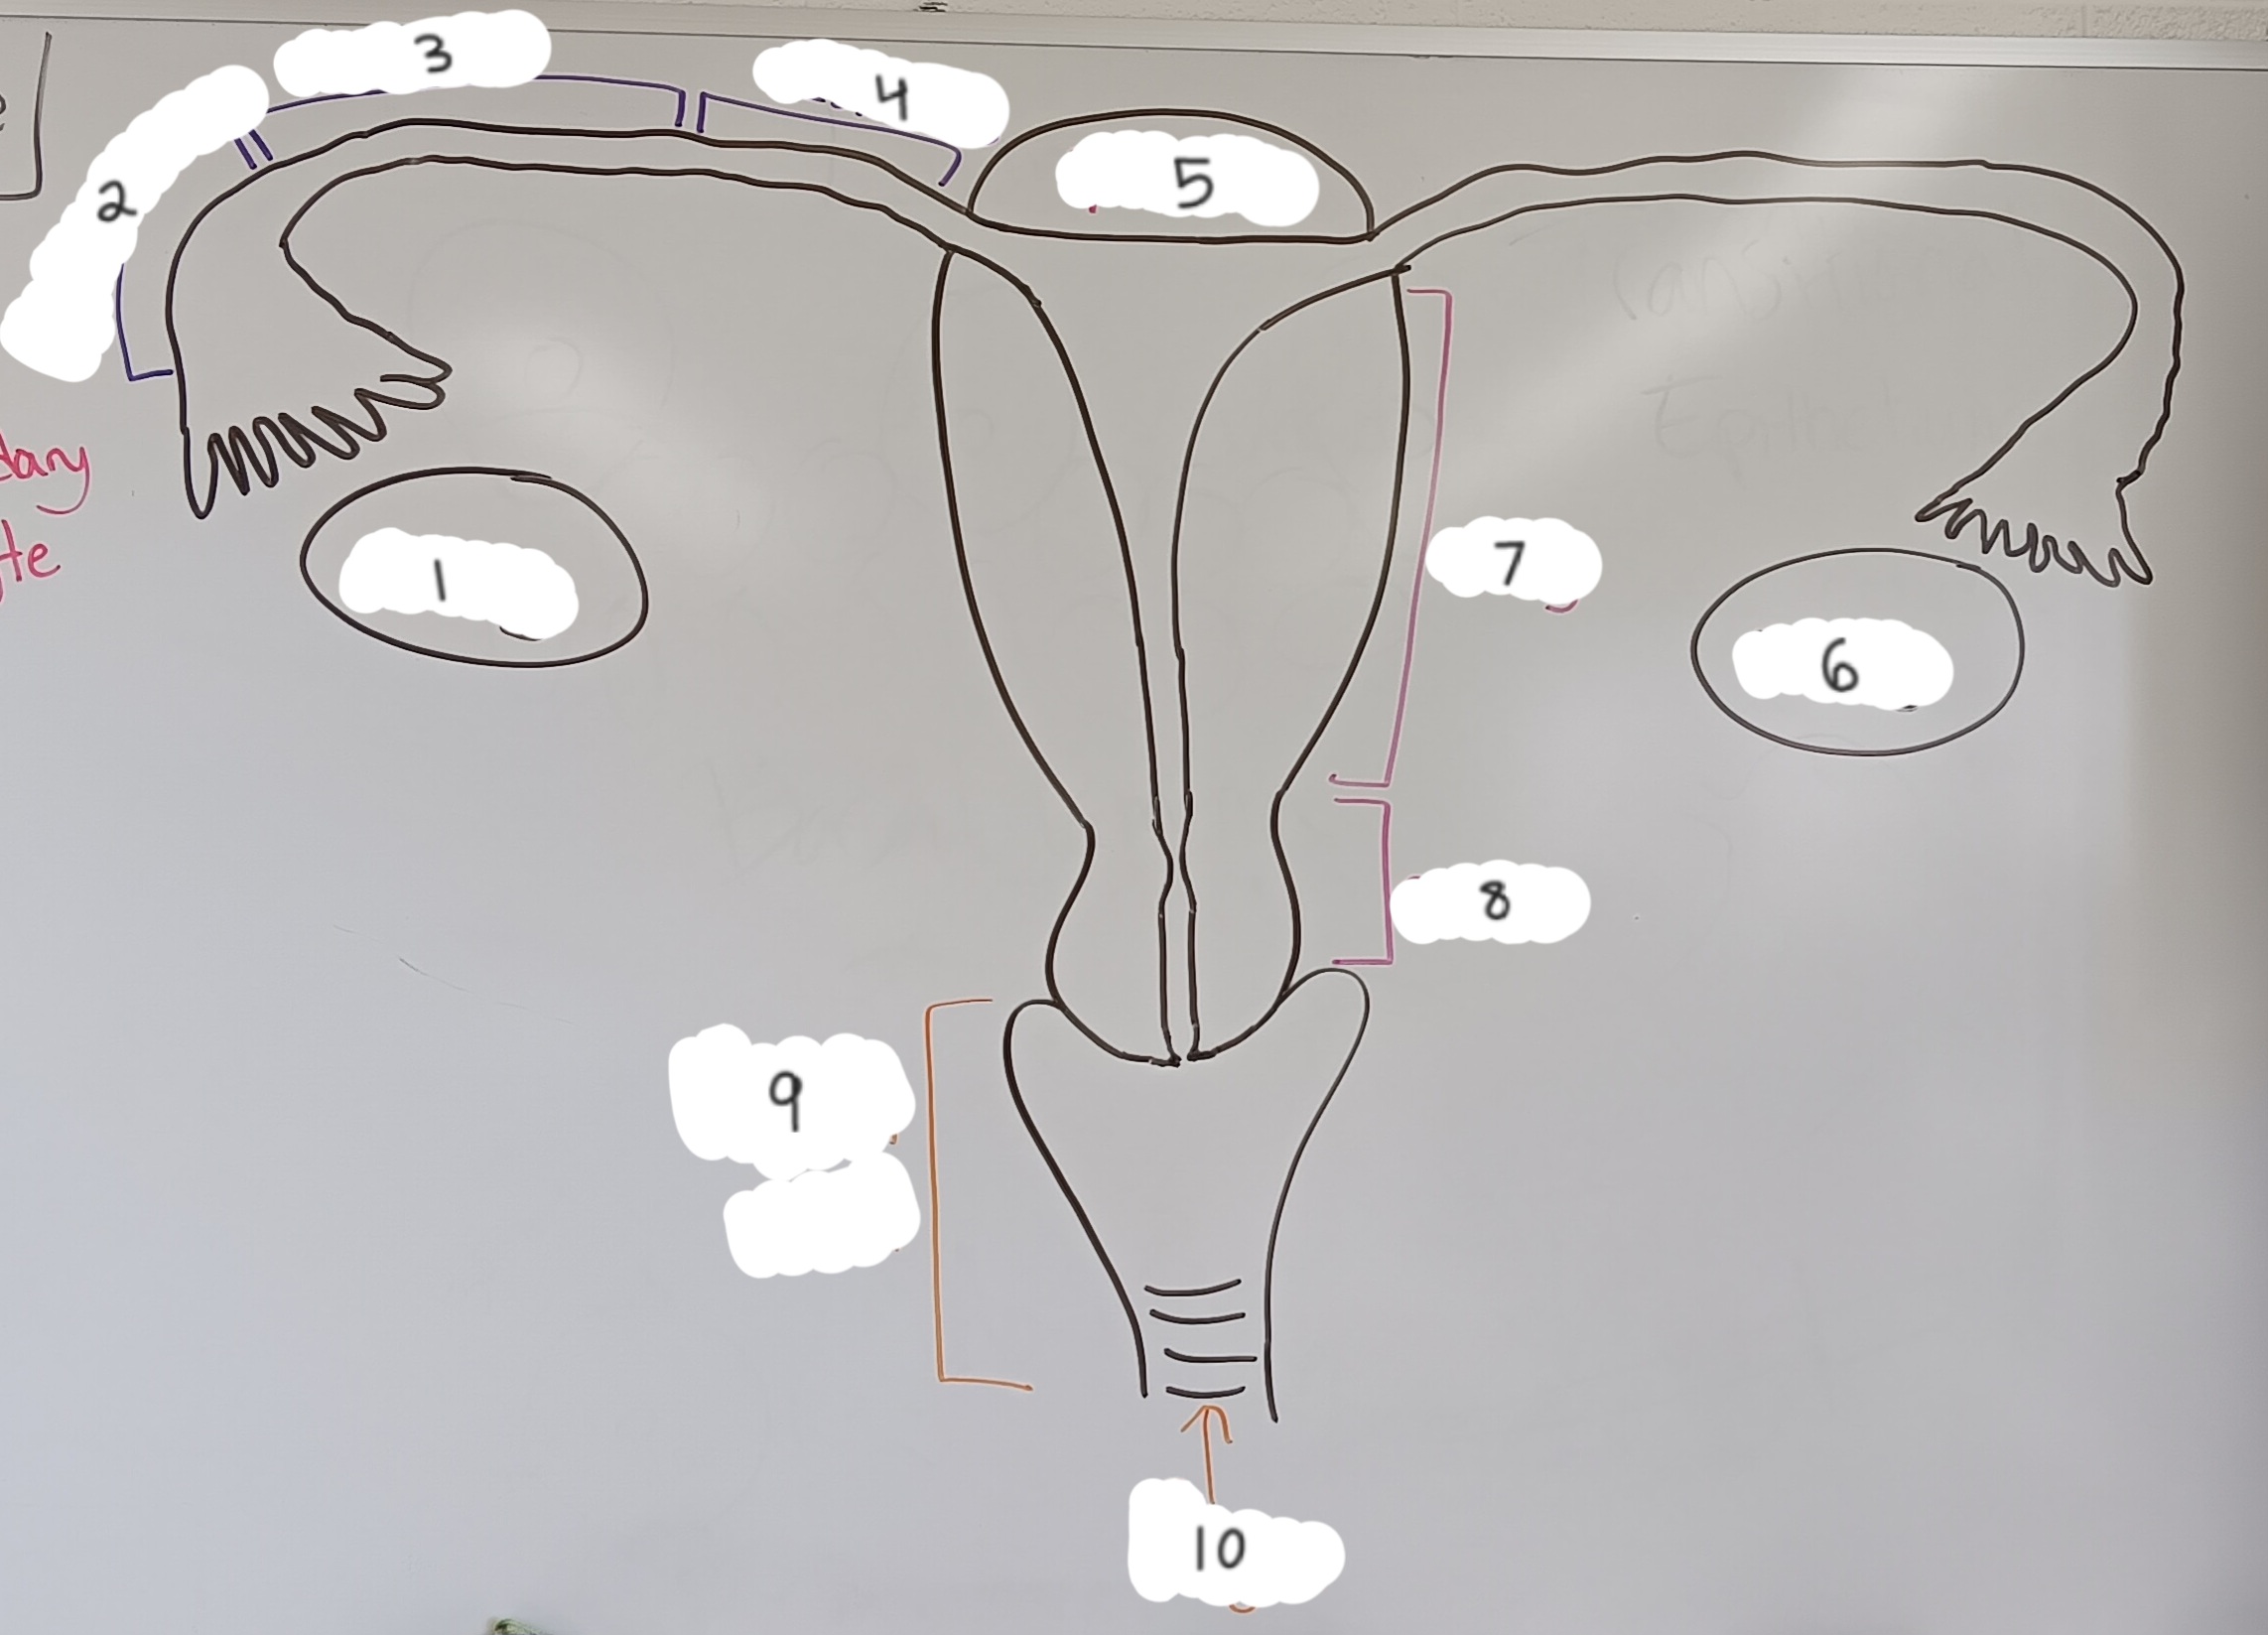

right ovary

1 (lt or rt)

infundibulum

2

ampulla

3

isthmus

4

fundus

5